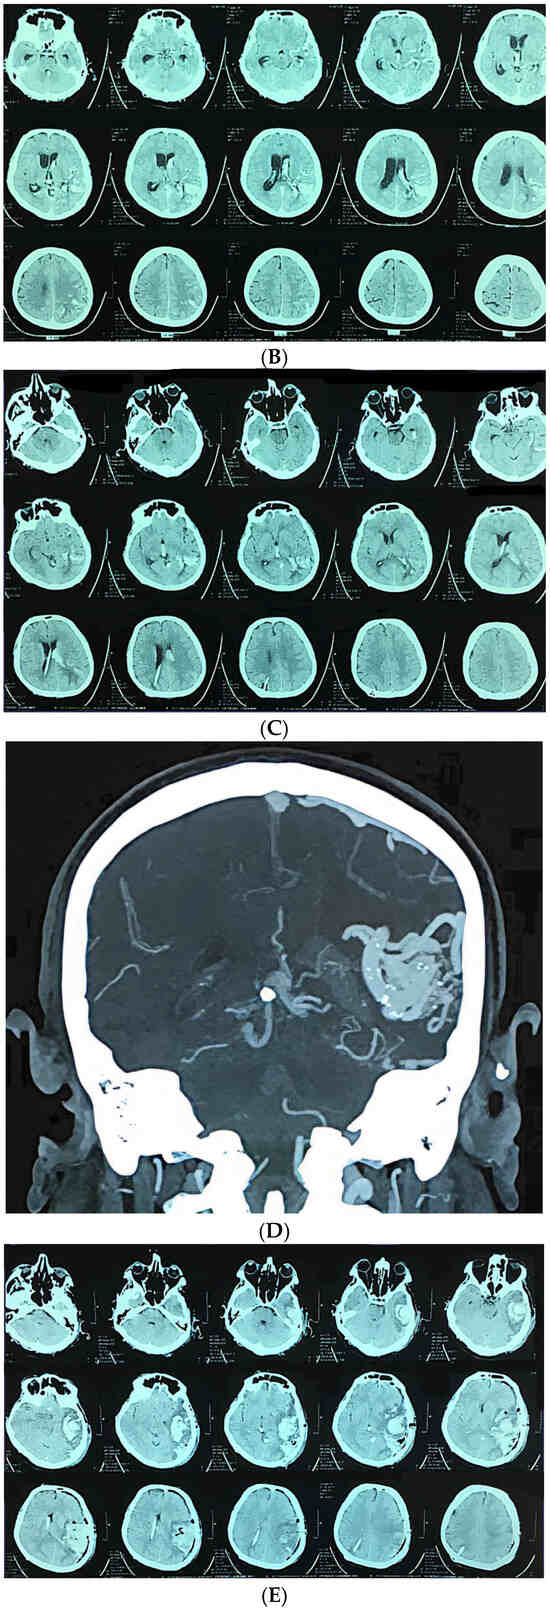

Figure 2.

A 65-year-old man presented with severe headache, nausea, vomiting, and impaired consciousness progressing to sopor. (A) Axial CT showing large ruptured right frontal arteriovenous malformation (AVM); (B) urgent CT angiography confirmed diagnosis; (C) postoperative computed tomography; (D) postoperative computed tomography angiography.